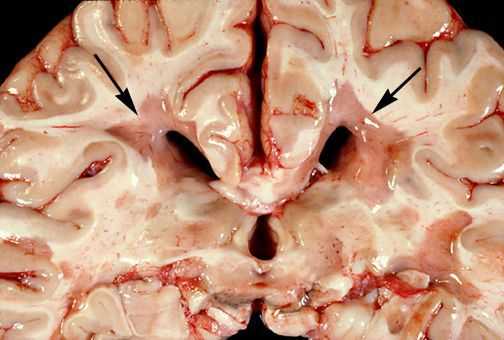

При микроскопическом исследовании обнаруживаются заметные и достаточно характерные изменения, выявляемые с наибольшим постоянством в спинном мозгу, мозговом стволе и полушариях головного мозга. Видны множественные бляшки различной величины (от точечных до весьма массивных, которые, к примеру, занимают весь поперечник спинного мозга), рассеянные преимущественно в белом веществе. Такая множественность и разбросанность очаговых изменений и определяет название болезни.

![Очаговые изменения в белом веществе мозга]()

Отдельные бляшки имеют округлую форму, они нередко сливаются и создают изменения сложных очертаний. Цвет бляшек на разрезе розовато-серый (недавно образовавшиеся очаги) или серый, желтоватый (старые очаги).

![Образовавшиеся бляшки]()

При разрезе бляшки определяется их большая плотность по сравлению с нормальной мозговой тканью. Эти уплотнения, склерозирование бляшек дало возможность охарактеризовать заболевание как склероз.